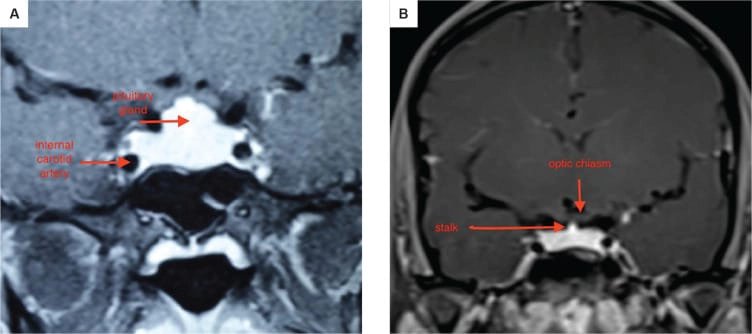

১. অবস্থান ও গঠন: পিটুইটারি গ্রন্থি একটি হাড়ের গঠন, যাকে সেলা টার্সিকা বলা হয়, তার ভিতরে বসে থাকে। এটি মাথার খুলির নিচের দিকে, স্ফেনয়েড নামক হাড়ে একটি গহ্বর, যা নাকের পেছনে অবস্থান করে। এটি অপটিক কায়াজম (optic chiasm) এর নিচে অবস্থিত, যেখানে দুটি চোখের স্নায়ু পরস্পর ক্রস করে। এটি ইন্টারনাল ক্যারোটিড আর্টারি নামক দুটি প্রধান রক্তনালীর মাঝখানে থাকে।

পিটুইটারি গ্রন্থি দু’টি প্রধান ভাগে বিভক্ত: অ্যান্টেরিয়র (সামনের) ও পোস্টেরিয়র (পিছনের) লোব। মানুষের ক্ষেত্রে ইন্টারমিডিয়েট লোব থাকলেও তা স্বতন্ত্র অংশ হিসেবে গঠিত নয়। অ্যান্টেরিয়র লোব অপেক্ষাকৃত বড় এবং পুরো গ্রন্থির প্রায় ৮০% ওজন ধারণ করে।